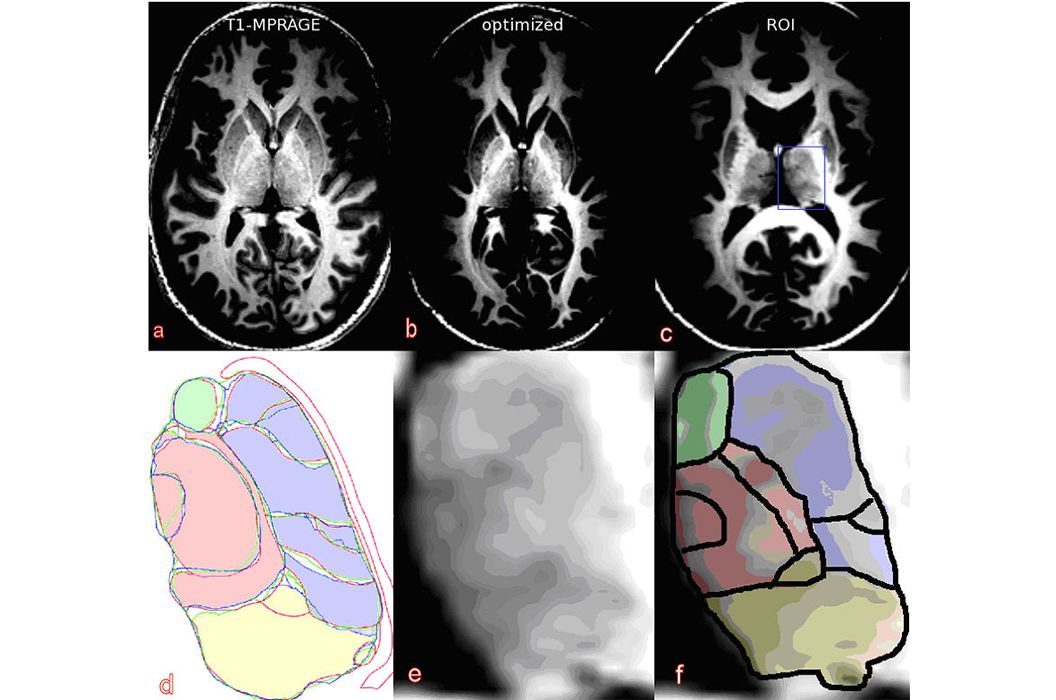

Die große Bedeutung der MR-Bildgebung für die radiologische Diagnostik beruht auf der sehr großen Variabilität des Kontrasts zwischen unterschiedlichen Geweben, der durch die Wahl der verwendeten Messsequenz bestimmt wird. Eine diagnostische Routineuntersuchung mit einem MR-Tomographen wird deshalb in den meisten Fällen mehrere Messsequenzen mit unterschiedlichen Signaleigenschaften enthalten. Dennoch können manche Strukturen im Körper nicht so differenziert abgebildet werden, wie es wünschenswert wäre. Eine dieser Strukturen ist der Thalamus.

Der Thalamus spielt eine wichtige Rolle als Zwischenstation von Afferenzen und Efferenzen der Großhirnrinde. Insbesondere bei Dystonien (Bewegungsstörungen) und dem Morbus Parkinson besteht die Möglichkeit, mittels Tiefenhirnstimulation in spezifischen Thalamuskernen eine Symptomverbesserung zu erreichen. Dabei werden auf diese Kerne elektrische Impulse über eine implantierte Elektrode übertragen. Um eine solche Elektrode richtig positionieren zu können, wird eine Bildgebungstechnik benötigt, die die Lage der Thalamuskerne zeigen kann.

Auf normalen anatomischen MR-Aufnahmen unterscheiden sich die Thalamuskerngebiete in ihrer Signalintensität jedoch zu gering, um sie identifizieren zu können. Das Ziel aktueller Forschungsarbeiten ist die Entwicklung von Messtechniken, die die Subeinheiten des Thalamus erkennbar werden lassen. Dabei werden besonders diffusionsgewichtete Sequenzen oder kontrastoptimierte 3D-Sequenzen untersucht.

Mögliches Promotionsthema: Markierung von Thalamussubgebieten in dreidimensionalen Datensätzen von gesunden Probanden und von Patienten und der Vergleich der Ergebnisse mit digital verfügbaren Informationen aus Anatomie-Atlanten.